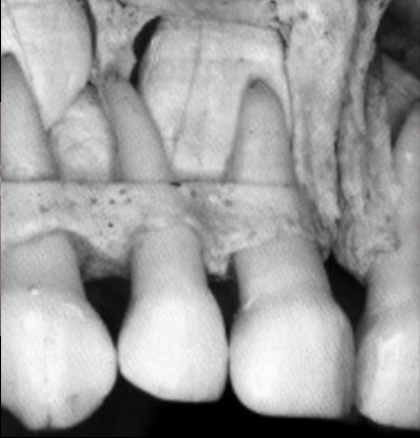

Examen radiologique retro alvéolaire :

Essentiel pour : diagnostic initial / suivi / aspect juridique.

Évaluation :

• Proximité pulpaire si perte de substance ?

• Évaluation du diamètre de la lumière canalaire ;

• Développement radiculaire ?

• Fracture radiculaire / alvéolaire ?

• Pathologie péri-apicale ?

• Traitement antérieur ?

• Rapport entre l’apex de la dent temporaire et le germe de la dent adulte ;

• Signes de résorption pathologique : externe, interne ;

+ Panoramique : en cas de choc sur le menton (Seule indication en traumatologie).